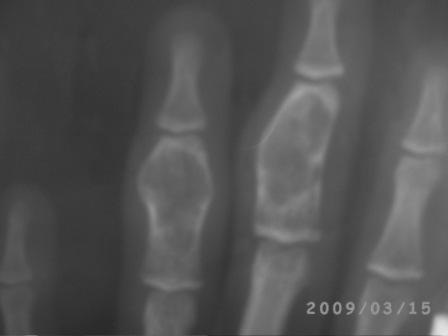

После Вашего послания сделал Р-граф. всей кисти, оказалось имеется патология 2 и 3 пястных костей!

Р-снимок прилагается.

Послеоперационные x-ray некачественные, всё ж кое что можно разглядеть, постараюсь повторно снять!

Стояние довольно приличное. Хорошо, что сохранили суставы. В такой ситуации вообще-то ничего и не придумаешь, кроме спиц. Поэтому я бы не менял метода фиксации. По снимкам больше похоже было на энхондрому, но вот меня смущает белесоватый цвет содержимого и кашицеобразная консистенция. Подождем гистологии.